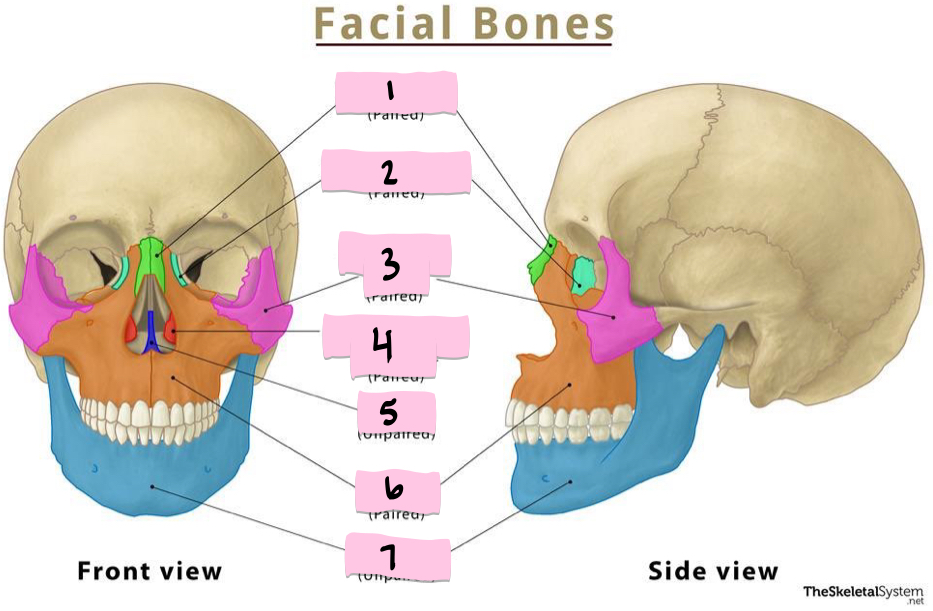

What is 1 pointing to?

Nasal bone

What is 2 pointing to?

Lacrimal bone

What is 3 pointing to?

Zygomatic bone

What is 4 pointing to?

Inferior nasal conchae

What is 5 pointing to?

Vomer

What is 6 pointing to?

Maxilla

What is 7 pointing to?

Mandible